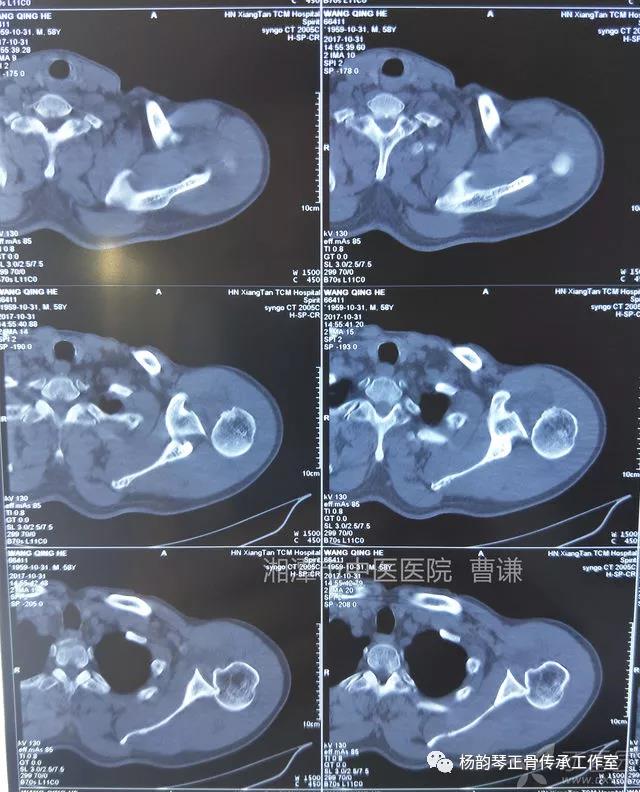

就诊我院后完善CT,诊断明确——左肩关节后脱位:

予以手法复位后拍片复查显示“灯泡征”消失,复位成功。讨论:肩关节后脱位在临床较为少见,特别是影像科经验不足很容易漏报,所以我们临床医生一定要自己仔细阅片,同时要结合体查来进行诊断,防止漏诊。肩关节后脱位时体查也有明显特征:肩关节前方明显变平,喙突较平时明显凸起容易触及,而肩关节后方明显丰满,上臂一般处于内旋内收位,无法主动外旋外展。肩关节后脱位的手法复位相对于前脱位的复位来说也比较容易。患者一般可以取坐位,助手自患侧腋下环抱患者稳定患者躯体,术者一手拉患肢上臂稍牵引内旋,一手自后方推顶肱骨头一般可以复位,如果单纯推顶无法复位也可以术者两手握住伤肢缓慢外展并沿肱骨纵轴牵引,然后逐渐外旋上臂即可复位。整复完成后可以把持患肢作肩关节各个方向的小幅度被动活动,防止肩关节粘连,肩关节后脱位的固定方法与肩关节前脱位的固定方法不同,应将患肢置于上臂外展、后伸、外旋位固定,即外展30度、后伸30度和轻度外旋位,用外展支架固定3周后,循序渐进开始肩关节功能康复。